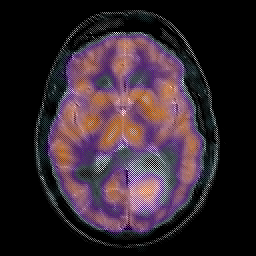

Glioma overlay -- Slice #14

[Home][Help][Clinical] Slice 14